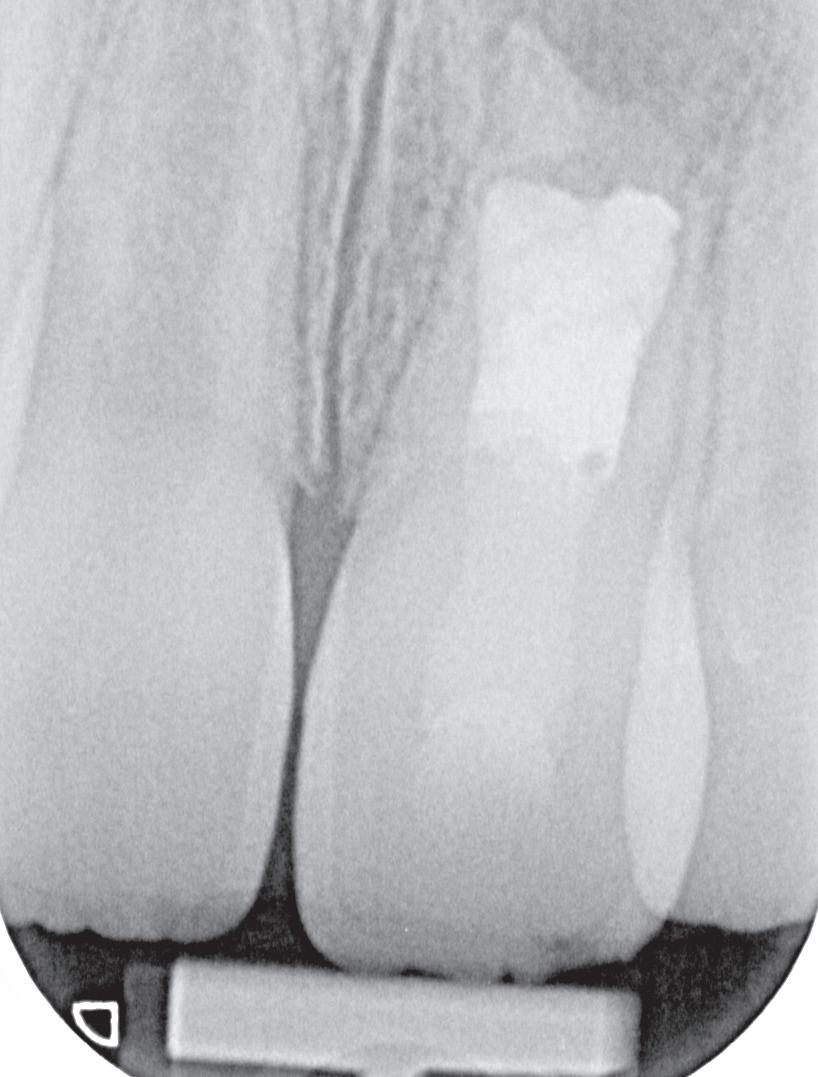

Je kan nu denken, heb ik nu net een gans artikel gelezen van een endodontoloog over hoe ik vooral geen wortelkanaalbehandelingen moet doen? Iemand die zo tegen zijn winkel spreekt kan waarschijnlijk gewoon geen goede wortelkanaalbehandelingen uitvoeren… Deze opmerking heb ik al een aantal keren gehoord wanneer ik een presentatie geef. Meestal begin ik dan ook met het tonen van een zeer uitdagende casus. In dit geval zal ik hetzelfde doen. Foto 1 is een recente wortelkanaalbehandeling die ik uitgevoerd heb. Zowat de natte droom van elke endodontoloog. Nu dat van de baan is, nog enkele voorbeelden uit de praktijk waarbij ik de patiënt centraal heb gezet en soms tegen de vraag van de verwijzende tandarts ben ingegaan.

De verwijzende tandarts wil tanden 24 en 25 overkronen en vraagt evaluatie en eventuele wortel-

kanaalbehandelingen en stiftopbouwen (foto 2). U ziet, mijn verwijzers zijn getraind en vragen eerst een evaluatie of het wel nodig is. Dit heeft me bloed, zweet en tranen gekost, alsook enkele verwijzers. Uiteindelijk bleek tand 24 vitaal te zijn en was er voldoende restweefsel om adhesief te werken. De wortelkanaalbehandeling op de 25 is misschien technisch niet ideaal, maar er zijn geen klachten of radiologische tekenen van infectie. In overleg met de patiënt is dus besloten om tand 24 te voorzien van een stompopbouw en tand 25 van een glasvezelstift en stompopbouw zonder te herbehandelen (foto 3). De tandarts kan onmiddellijk verder met de kronen.